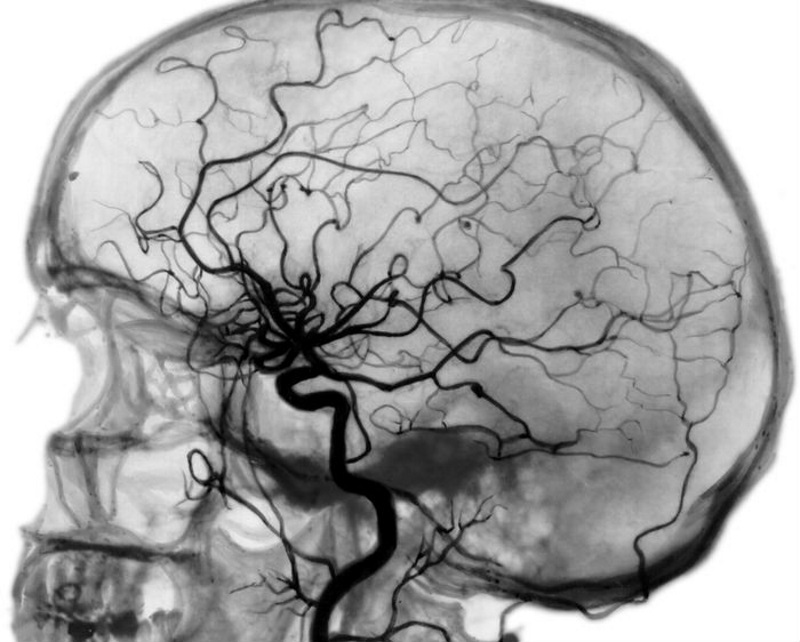

Комп’ютерна ангіографія (КА)

Маніпуляція супроводжується рентгенівським опроміненням. Хворому в артерію вводять хімічний препарат. Спеціальним приладом знімають зображення судини, вени або артерії зсередини. Цей метод забезпечує високу точність діагностики, дозволяє вивчити самі дрібні судини.

За допомогою ангіографа можна отримати зображення голови в горизонтальному зрізі. Використовується перед складними операціями, пов’язаними з нервовою системою.